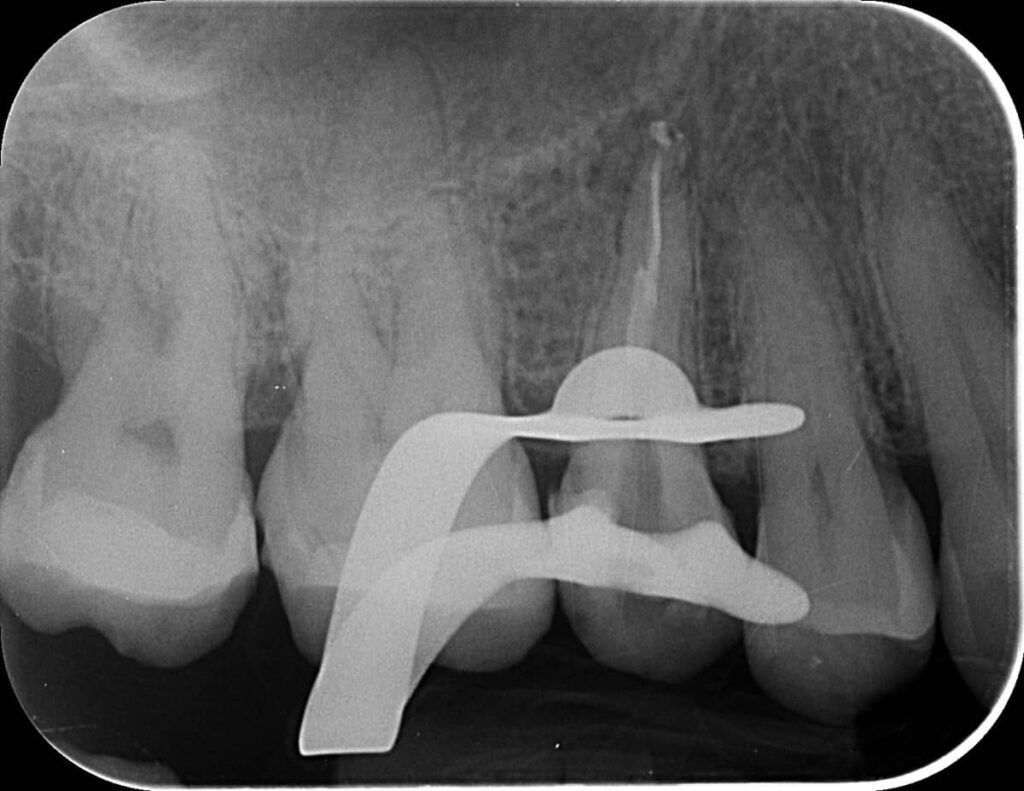

A következő alkalommal alaposan átfertőtlenítettük a csatornákat. Itt már láttuk is, hogy tényleg közös utolsó szakasszal rendelkeznek. Protokoll szerint ismét röntgenfelvétel következett, mellyel ellenőriztük a kiválasztott későbbi gyökértömő pálcika méretét.

mikroszkópos gyökérkezeléssel megmentett fog: a bent rekedt fragmentumok eltávolítása 4